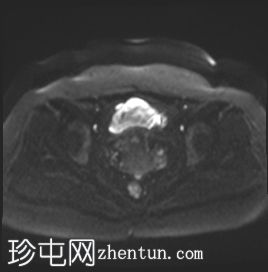

MRI

矢状位

T2加权像

可见子宫外腹腔内妊娠囊,内含胎儿组织。

该妊娠囊向后推移子宫,并与剖宫产瘢痕凹陷处紧密相连。

该妊娠囊与相关肠袢无法分离。可见其与性腺血管密不可分,且性腺血管明显突出。

胎盘位于妊娠囊后方,紧贴子宫前壁。

沿妊娠囊下缘可见一处异质性局灶性积液,最大轴向尺寸约为 8.4 × 5.5 cm,T1 加权像呈异质性高信号,T2 加权像呈异质性中等信号,T1 脂肪抑制序列未见信号下降,提示为血液成分。该积液压迫膀胱。

可见周围脂肪间隙呈条索状改变。

左侧卵巢无法辨认。

右侧卵巢未见实性或囊性肿块。

子宫体积增大,后倾,子宫内膜厚度约 1 cm,子宫下段前壁可见局灶性变薄(既往子宫瘢痕)。子宫连接区完整,未见肌层肿块。可见子宫内膜腔边缘有血性分泌物。